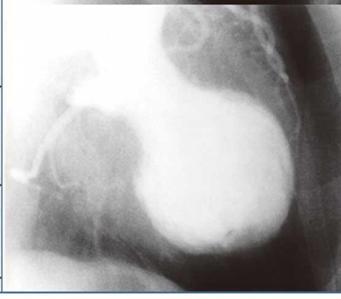

Заболевание напоминало инфаркт, и на ультразвуковом исследовании сердце выглядело так, как будто это был горшок для ловли осьминогов, широко применяемый в Японии.

Так выглядит сердце при выполнении исследования Левого желудочка сердца с контрастом.

Поэтому заболевание назвали «Кардиомиопатия такоцубо», что в переводе с японского означает - приспособление для ловли осьминогов - tako-tsubo.